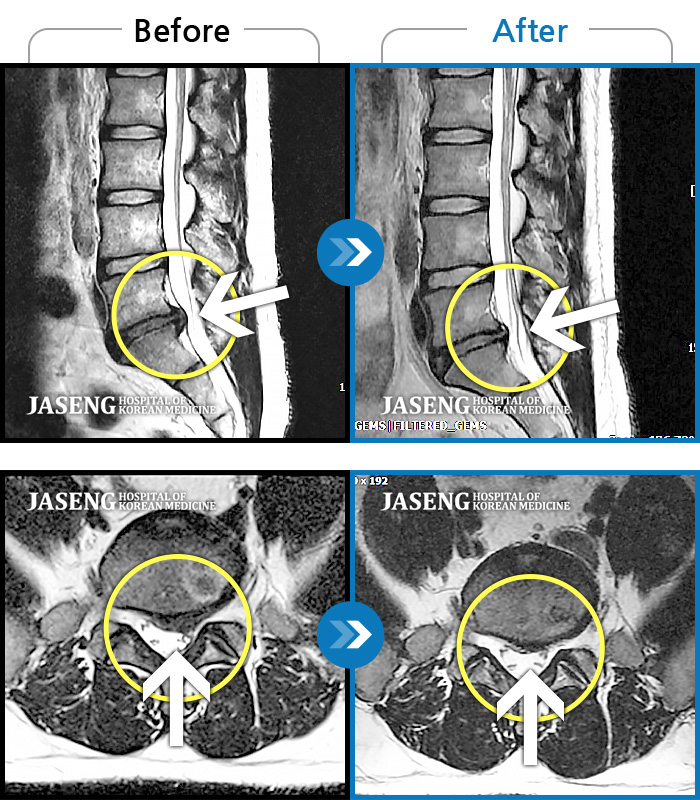

허리디스크

목동 · 고웅 원장

왼쪽 허벅지부터 발가락까지 아프고 저려 일상생활 불가능한 상태

촬영시기

2021.03.27 ~ 2023.04.10

2023.12.08